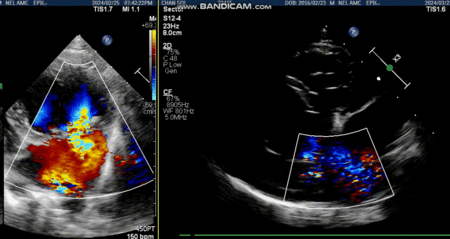

심정지까지 이루어지면 좌심방을 절개하고 들어가 판막과 건삭 상태를 확인한다. 이때 수술자는 건삭파열의 위치 및 판막의 퇴행성 변화를 확인하고 적절한 수술 방법을 선택하여 이첨판막 재건술을 실시한다. 판막 기능의 수복이 완료되면 심장을 다시 뛰게 하고 체외순환기의 역할을 줄이는 weaning 과정을 거친다. weaning 과정을 마치고 폐흉이 이루어지면 모든 수술 과정이 마무리된다.

수술 후 모든 환자는 이첨판 역류의 대부분이 소실되어 생리적 수준의 MR만이 남았으며, 모든 환자들은 수술 직후 이뇨제를 단약함과 동시에 심장 리모델링이 빠르게 진행되었다. 술 후 1주-1달 정도가 지나면 더 이상 피모벤단이 필요하지 않은 경우가 대부분이었다. 또한 환자들은 술 후 3개월이 지나면서 내복약을 복용하지 않게 되었고, 3개월이 지나지 않은 환자는 내복약을 중단하는 과정에 있다.